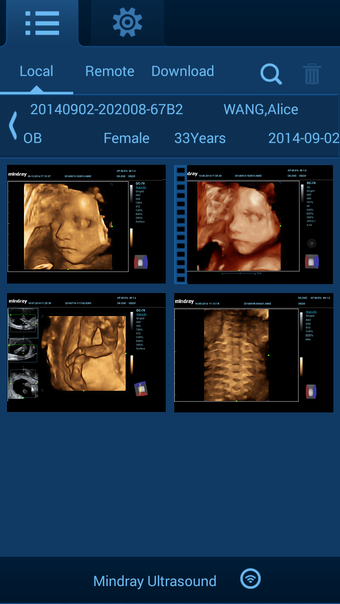

Uygulama birkaç faydalı özellikle birlikte gelir. İlk olarak, kullanıcılar ultrason sistemine kaydedilen hasta bilgilerini uzaktan inceleyebilir ve hasta verilerini indirebilir. İkinci olarak, kullanıcılar hasta verilerinin indirme ilerlemesini ve durumunu kontrol edebilir. Üçüncü olarak, kullanıcılar ultrason görüntüleri ve sine döngüleri de dahil olmak üzere hasta verilerini yerel olarak gözden geçirebilir. Son olarak, uygulama temel ayarlama fonksiyonları ve yazılım bilgileri sağlar. Uygulama kullanımı kolaydır ve hastaların akıllı cihazlarında ultrason görüntülerine ve sine döngülerine erişmeleri için pratik bir yol sunar.